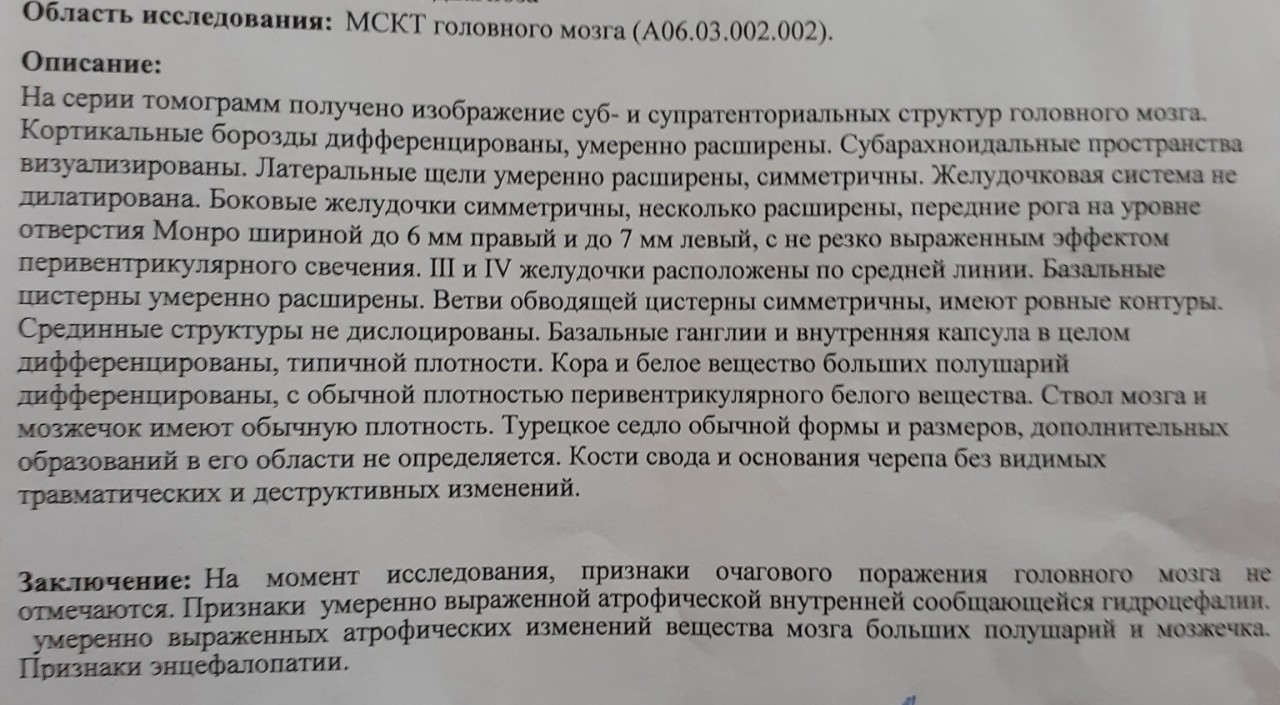

Признаки умеренно выраженной наружная

Признаки умеренно выраженной наружная 113 фото